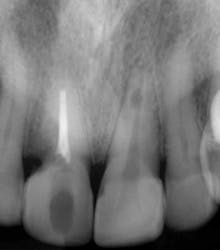

Fig. 1 — Preoperative radiograph demonstrating an internal resorptive defect in the apical third of the root in tooth No. 9. Note the cervical resorptive lesion in tooth No. 8.